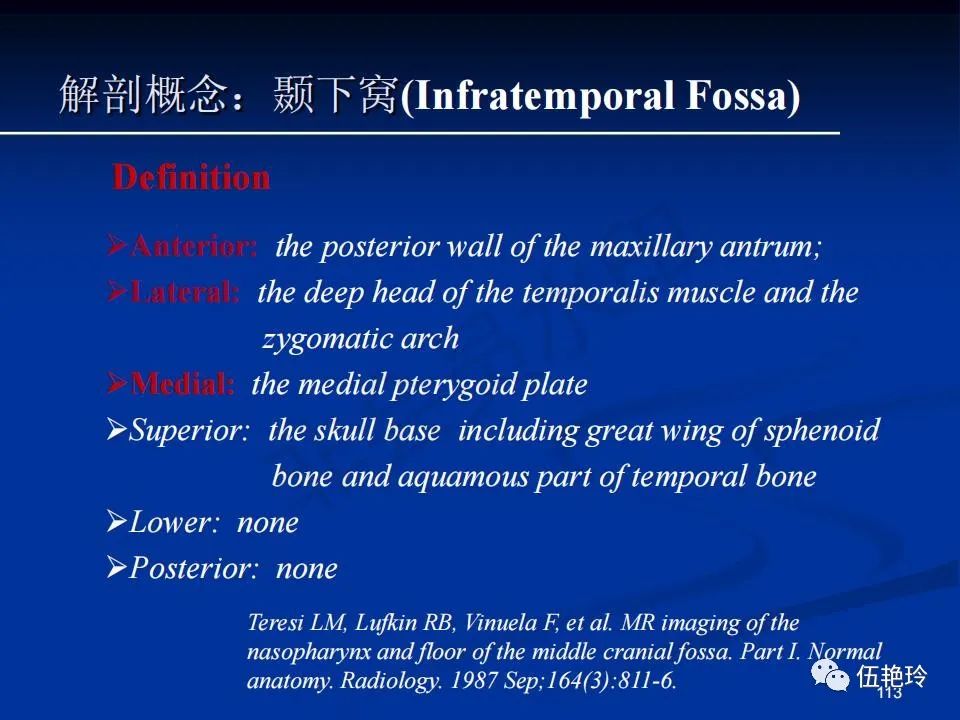

颞下窝与咀嚼肌间隙

2.31 向上颅内:①鼻咽顶壁→破裂孔(岩尖、斜坡)→蝶窦、海绵窦;②鼻咽顶壁→蝶骨基底部→蝶窦、海绵窦;③鼻咽侧壁→茎突前间隙→蝶骨大翼(卵圆孔)→海绵窦;④鼻咽侧壁→茎突前间隙→翼腭窝→ 颞下窝;⑤鼻咽前壁→鼻腔→翼突、翼腭窝→眶下裂→眶尖→海绵窦;⑥鼻咽前壁→鼻腔→上颌窦、筛窦;